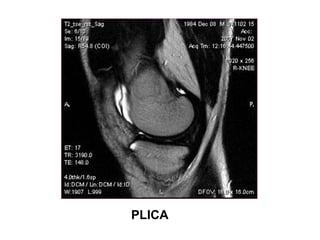

PLICA